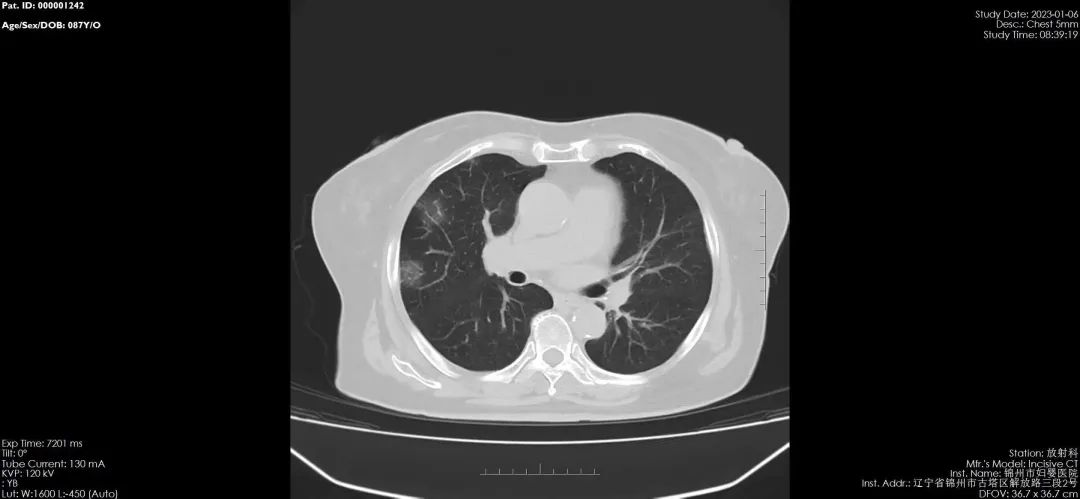

【医疗时讯】CT对病毒性肺炎的检查优势

锦州市妇婴医院(妇幼保健院)放射线科,于2020年引进国内最新进口飞利浦64排128层螺旋CT,扫描速度快、分辨率高、层数更薄,对病毒性肺炎有着更高的检出率和准确率,可以更好的与其他肺炎进行区分,对早期肺炎治疗有着非常重要的临床意义。